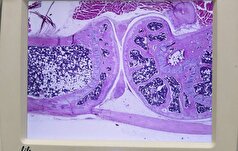

برخی از مو‌ها به جای اینکه از پوست خارج شوند و بیرون از آن رشد کنند، زیر پوست می‌مانند. در اثر باقی ماند مو‌ها در زیر پوست ممکن است کیست تشکیل شود. کیست نیز به کیسه‌ای کوچک از بافت بدن گفته می‌شود که روی پوست ایجاد شده و با مایع یا چرک پر می‌شود. کیست مویی رشد کرده نیز زمانی اتفاق می‌افتد که این کیست در اطراف مو‌های رشد کرده در زیر پوست ایجاد شود. این حالت بیشتر در شرایطی ایجاد می­شود که مو‌ها با تیغ اصلاح شده باشند که با نام pseudofolliculitis barbae نیز شناخته می­شود و آن شکلی از کیست‌های مویی رشد کرده است.

کیست‌های مویی رشد کرده شبیه به آکنه‌های کیستیک نیستند، زیرا این کیست‌ها در واقع برآمدگی‌هایی هستند که در زیر فولیکول‌های پوست به دلیل تجمع باکتری‌ها، چربی و سلول‌های مرده پوست ایجاد شده اند.

کیست‌های مویی رشد کرده در زیر پوست بیشتر در نواحی از بدن که مو‌هایی ضخیم یا مجعد دارد، مانند ناحیه شرمگاهی، ایجاد می‌شود. بنابراین، اگر مو‌های ضخیم یا مجعدی دارید، ممکن است بیشتر در معرض ابتلا به کیست‌های مویی رشد کرده در زیر پوست باشید. همچنین آن‌ها ممکن است در مناطقی ایجاد شوند که سلول‌های مرده پوست فولیکول‌های مو را مسدود می‌کنند.